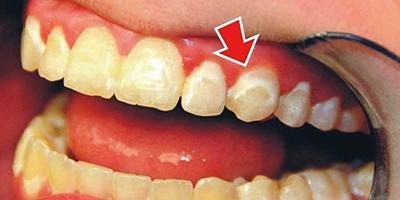

Фото 1. Снимок зубов взрослого человека с прогрессирующим на них кариесом начальной стадии.